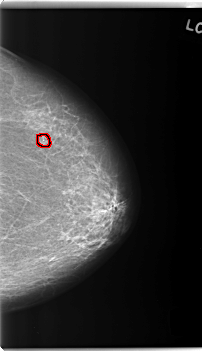

C_0231_1.LEFT_MLO

FILE: C_0231_1.LEFT_MLO.OVERLAY

TOTAL_ABNORMALITIES 1

ABNORMALITY 1

LESION_TYPE CALCIFICATION TYPE PLEOMORPHIC DISTRIBUTION CLUSTERED

ASSESSMENT 4

SUBTLETY 5

PATHOLOGY BENIGN

TOTAL_OUTLINES 1

BOUNDARY